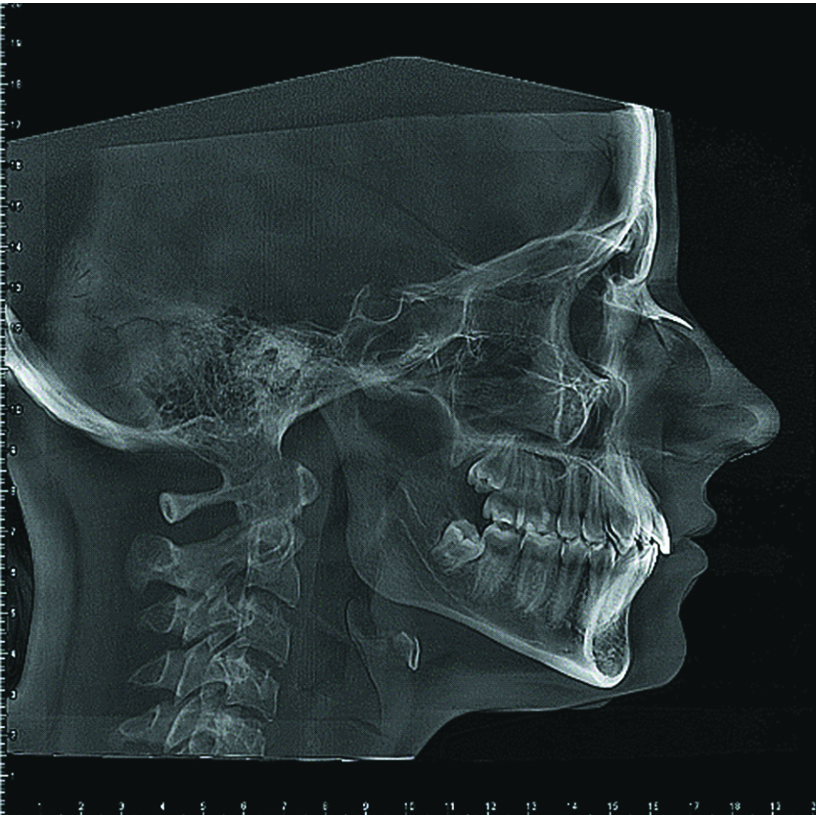

Было обследовано 25 пациентов (возраст от 12 до 40 лет) с дистальной окклюзией. Обследование проводилось согласно протоколу, который включен в «Историю болезни ортодонтического больного», разработанную на кафедре ортодонтии ФГБОУ ВО «Российский университет медицины» и утвержденную приказом Минздрава России №834. После осмотра участники исследования прошли телерентгенографию (ТРГ) головы в боковой проекции (рисунок 1).

Рисунок 1. ТРГ головы в боковой проекции.

Figure 1. Lateral cephalometric radiograph of the head.